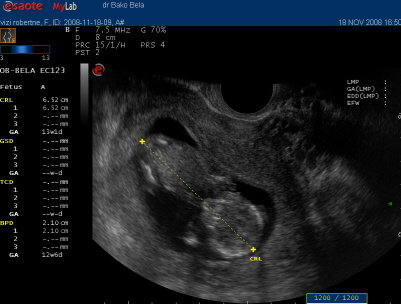

Pumukli!